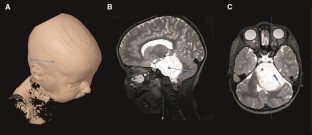

Fig. 1